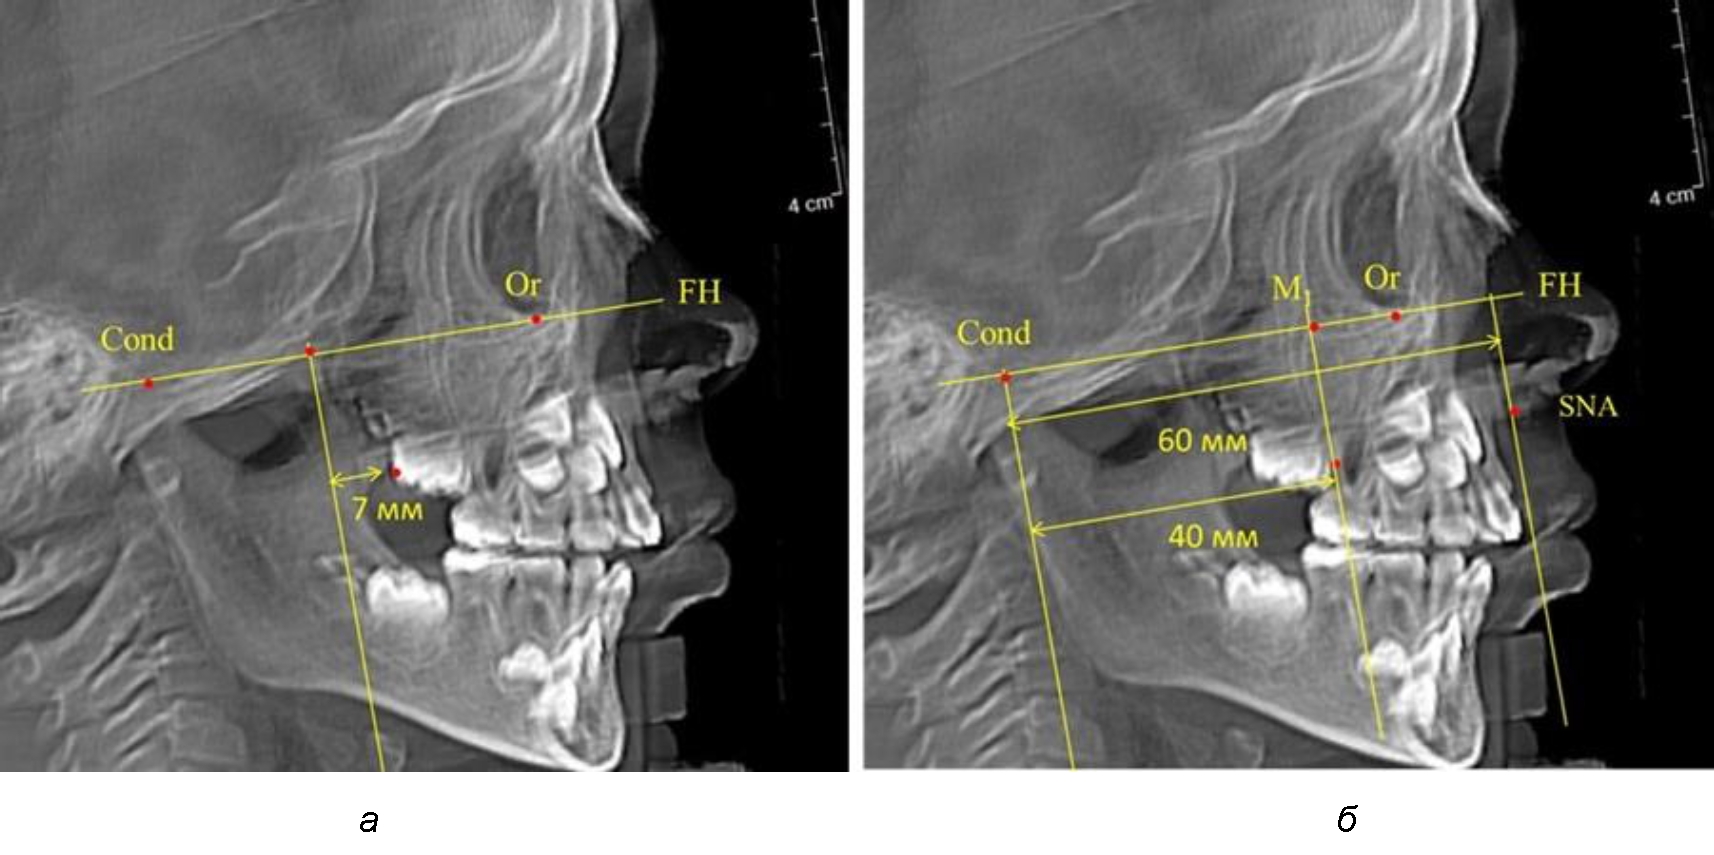

Рис. 4. Особенности положения первых моляров по R. E. McDonald (а) и по предложенному методу (б) у ребенка 4 лет

Второй частью исследования был анализ положения первых постоянных моляров в различные периоды сменного прикуса. На телерентгенограммах детей периода прикуса молочных зубов дистальная поверхность зачатка первого постоянного моляра отстояла от крыловидной вертикали на величину, составляющую около 7 мм, что было близким по значению к данным R. E. McDonald. Сагиттальный размер гантического отдела составлял около 60 мм, а его отношение к кондилярно-молярной глубине – 1,5 (рис. 4).